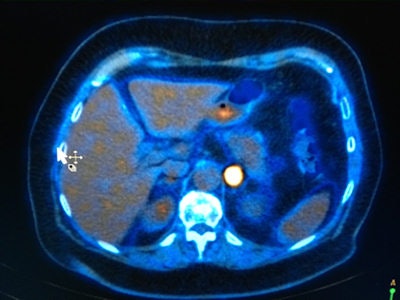

A shift toward nuclear medicine technologies is occurring. This PET/CT image shows abnormal uptake of isotope in the left para-aortic region. Image courtesy of Dr. Richard Fowler.If trainees only get trained in one modality then they are missing out on the other areas, he explained in a keynote titled "Radiology 20/20 vision: Will science fiction become reality?" New training pathways are necessary for trainees to become research-competent, as well as enabling them to drive the research forward.

Fowler noted that since x-rays were developed, the vast majority of imaging has been structural and anatomical, but this has shifted to PET/CT and other nuclear medicine technologies. "In the future, this will expand to new techniques such as molecular imaging for targeting specific disease processes such as those involved in inflammatory diseases and cardiovascular diseases, as well as cancers that already use advanced imaging techniques."

In parallel, there will be new ways of dissecting out gene sequences, and it will be essential to become more specific with imaging diagnostics, he added. Currently, MI is mainly used in PET/CT for cancer diagnosis, providing excellent images from which to make a diagnosis and monitor response to treatment. In this era of personalized medicine, having decided that a patient has a subtype of disease, that subtype will be targeted by a variety of investigative agents and MI will evaluate which actually works, he explained.